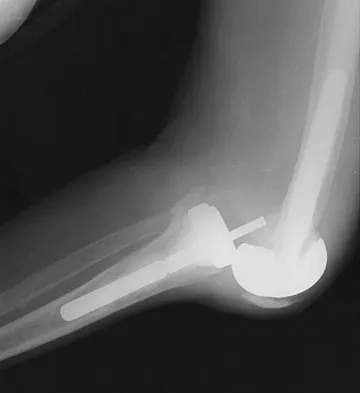

Figure 3 shows the radiographs of a 32-year-old man who fell 12 feet onto his outstretched arm and sustained a fracture-dislocation of the elbow. Initial management consisted of closed reduction of the dislocation. Surgical treatment should now include repair or reduction and fixation of the

Explanation

The radiographs show fractures of the coronoid and radial head. The medial collateral ligament has been avulsed from the ulnar insertion, and there is a valgus opening on the medial side. The lateral collateral ligament is always disrupted in elbow dislocations and fracture-dislocations that occur secondary to falls. This is known as the terrible triad injury (dislocation and fractures of the coronoid and radial head); it has a very poor prognosis because of its propensity for recurrent or persistent instability and late arthritis. The principle in treating this injury is to repair all of the injured parts or protect them with a hinged external fixator until they heal. Norris TR (ed): Orthopaedic Knowledge Update: Shoulder and Elbow. Rosemont, IL, American Academy of Orthopaedic Surgeons, 1997, pp 345-354. Kasser JR (ed): Orthopaedic Knowledge Update 5. Rosemont, IL, American Academy of Orthopaedic Surgeons, 1996, pp 283-294.